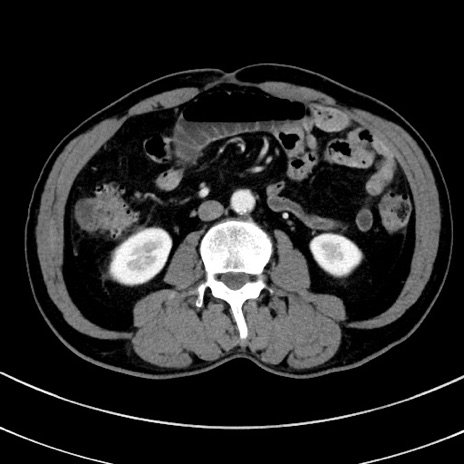

症例8(横断像)

【症例】 60歳代男性

【主訴】 黒色吐物

【現病歴】 4日前から嘔気自覚、2日前の朝食後にも嘔気あり、自分で手で嘔吐反射起こし嘔吐したところ血が混ざっていたため受診。

【既往歴】 5年前汎発性腹膜炎を伴う急性虫垂炎で手術、高血圧、前立腺肥大症、高脂血症

【身体所見】 腹部正中に手術癩痕あり 腹部平坦・軟圧痛なし膨満感あり

【データ】WBC 8400、CRP 4.54